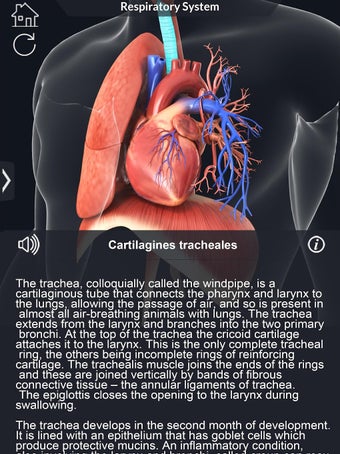

呼吸器系の解剖学は、肺、気管、およびすべての気道を含む呼吸器系の解剖学の研究です。最も一般的なアプローチは、系を上部と下部に分割することです。上部には気管、主気管支、および終末および前頸気道が含まれます。下部には肺と最小の大きさの末梢気道が含まれます。これらの部分それぞれには特徴的な外観と機能があります。

このアプリケーションは、高度にリアルな呼吸器系のモデルです。ユーザーは任意の角度および任意の平面から呼吸器系の解剖学を表示できます。ユーザーは360°回転し、ズームインおよびズームアウトして解剖学をよりよく研究することができます。ユーザーはまた、画面に描画するためのさまざまなツールを使用して写真を撮ることもできます。